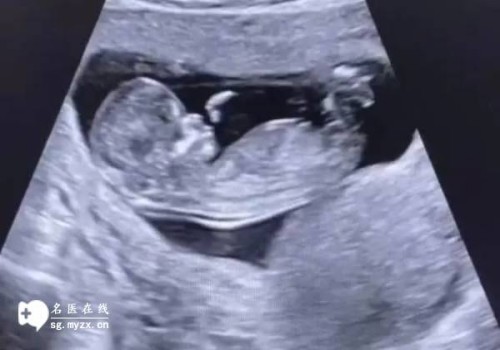

2022多胎妊娠对是吃保胎药还是减胎对女性的身体更好?对于多胎妊娠有减胎的必要性,但也不是绝对的。一般出现多胎妊娠后,会增加出现流产、早产、胎儿发育畸形、妊娠并发症等几率。

在优生优育方面,试管婴儿的目标是:足月,单胎,健康的孩子。所以,发现三胎的时候,一定要尽早减掉,以确保母婴安全。减胎术并不是终止妊娠,而是一种能取得更好结果的方法。

减胎术有两种方式,一种是经腹减胎,一种是经阴道减胎。前一种情况适合怀孕月份比较大,如怀孕三个月及以上,或者是有阴道减胎手术禁忌者;后一种情况适合于怀孕3个月以内的病人,一般来说,怀孕月份越小,成功